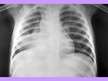

Mycobacterium tuberculosis morfoloģija, genoma uzbūve, fizioloģija un bioķīmija